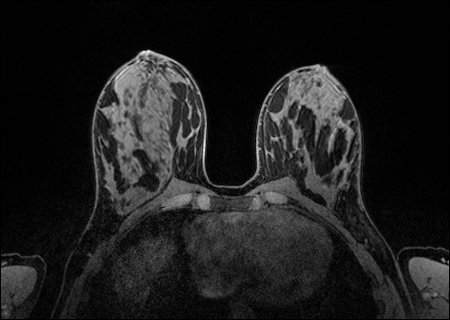

Herston Imaging Research Facility (HIRF) is now home to a new 18 channel breast coil for MRI, which delivers brilliant image quality and is better able to visualise masses in dense tissue.

The HIRF team are thrilled to have this new equipment available for clinicians and researchers looking to further examine abnormalities found during mammogram or ultrasound.

Breast MRI is a valuable technique to help identify cancer in high-risk patients and can also determine the extent of a known cancer in the breast. This new coil will enhance our breast imaging research capabilities and allow us to participate in multi-site clinical trials.